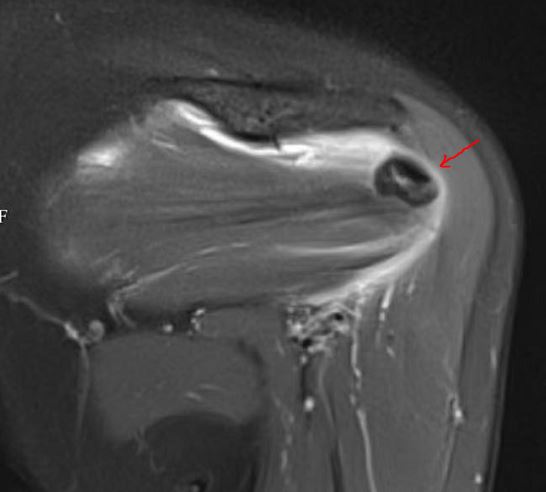

MRI 上钙化灶为低信号影(黑色的)